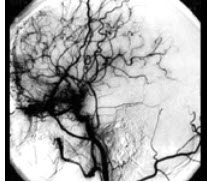

25岁脑室出血患者, 行脑DSA发现如图所示血管,这种血管图称为__________。